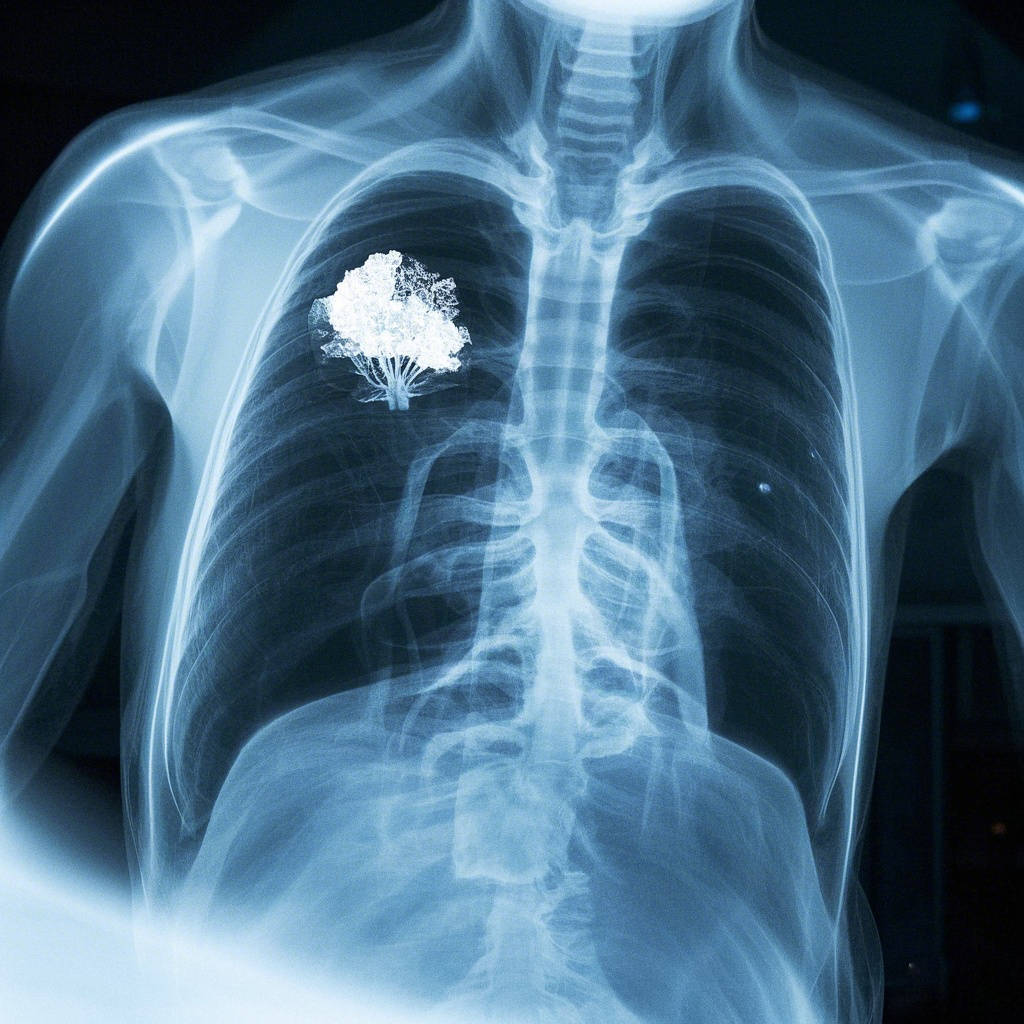

在人体的呼吸中枢——肺部,藏着一群极易被忽视的“潜伏者”,它们形态微小、毫无征兆,却可能在不知不觉中侵蚀肺部健康,这就是肺结节。随着体检手段的普及,越来越多人在胸部CT报告上看到“肺结节”三个字时,难免陷入恐慌与困惑。有人将其与肺癌画上等号,整日忧心忡忡;也有人觉得无症状便无需理会,放任其发展。事实上,肺结节既是需要警惕的健康信号,也并非所有结节都意味着危险,科学认知与规范应对才是破解这一“肺内隐患”的关键。

面对肺结节,科学筛查与精准判断是前提。目前,胸部低剂量CT是筛查肺结节的首选方式,其辐射剂量低、分辨率高,能发现直径1毫米以上的微小结节,较胸部X光片更精准,可有效提高早期结节的检出率。对于体检发现的肺结节,医生会根据结节的大小、形态、密度、生长速度等指标,结合患者年龄、吸烟史、家族病史等因素,综合判断结节的良恶性风险,制定个性化的应对方案。